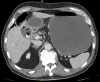

Gastric outlet obstruction in a patient